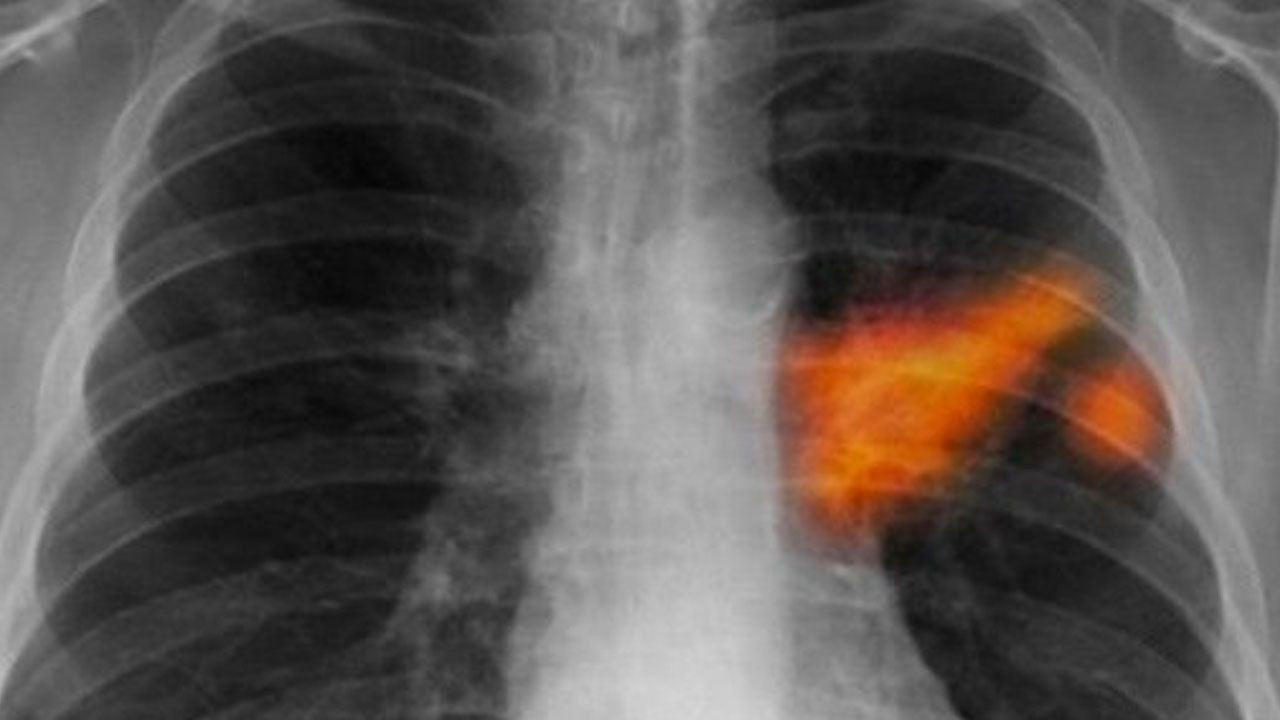

Çapı 2,5 mikrometreden daha küçük partikül maddelerin PM2,5 olarak adlandırıldığını, gözle görülemeyecek kadar küçük olan bu maddelerin akciğerlerin en uç noktalarına kadar ulaşabildiğini ve hatta solunduktan sonra kana karışabildiğini belirten Laçin, şöyle devam etti: